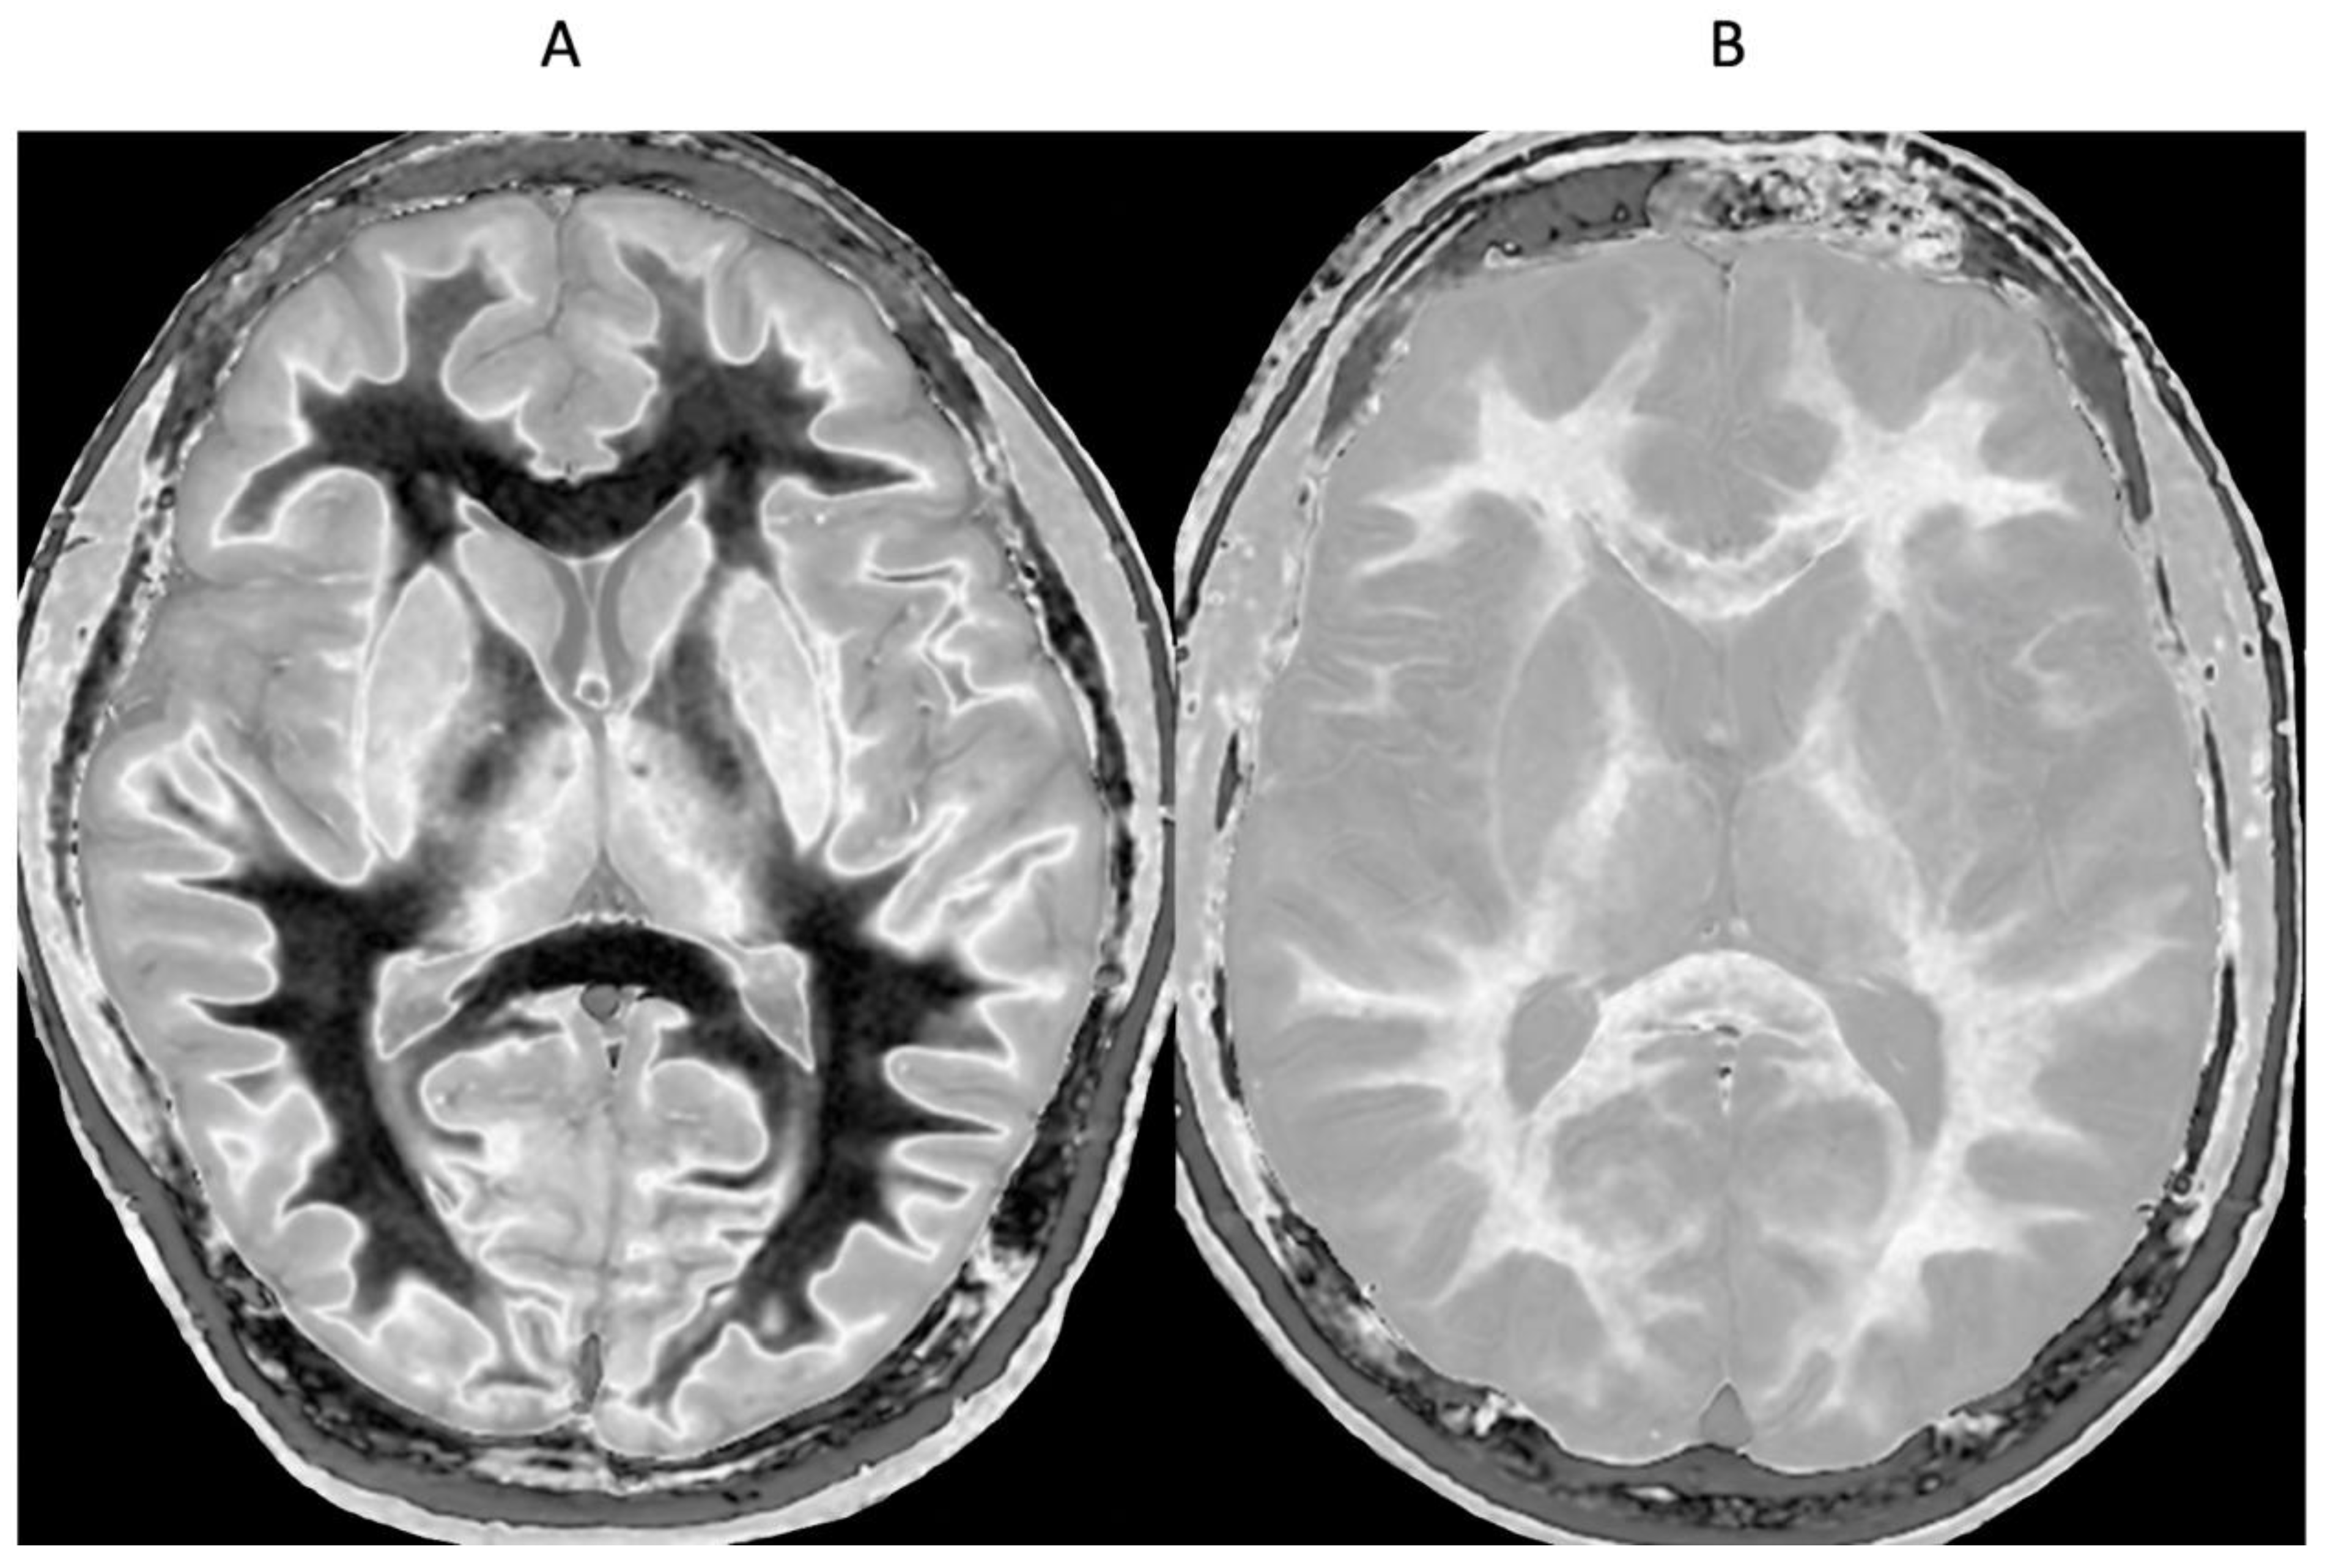

Figure 13.

Normal control (A) and patient with mTBI (B) showing a whiteout sign and grayout signs (narrow mD dSIR [T1-BLAIR] images). The normal control shows the heads of the caudate nuclei with higher signal than the adjacent CSF. Contrast is also seen between the cortex and CSF. In (B), the patient shows a whiteout sign. There are grayout signs in the thalami and putamina. In addition, contrast between the heads of the caudate nuclei and CSF is reduced and there is little or no contrast between cortex and CSF which are isointense. These are also grayout signs. No abnormality was seen on the T2-FLAIR images in the normal control or patient.